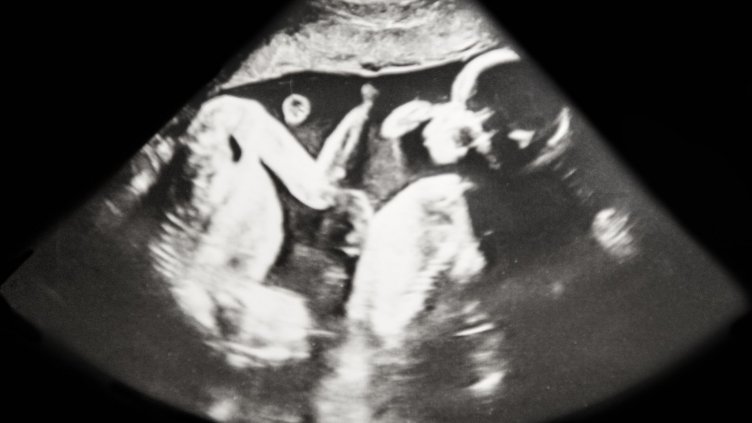

Болницата "Ихилов" в Тел Авив съобщи, че жена с две матки е родила две близначета - по едно във всяка, предаде ДПА, цитирана от ДИР.bg. Така бебетата са се "срещнали" чак след раждането.

Жената, която е на 31 години, е родена с двойна матка. При това състояние обичайната матка е разделена в средата. Раждане на близначета в такива случаи е извънредно рядко. Вероятността е около едно на милион.

Бременността е наблюдавана много отблизо, защото е била с висок риск. Раждането е било със секцио през 35-ата седмица.

Жената е научила за двойната си матка, когато е била на 20 години. Преди да забременее, тя се е притеснявала, че бебето ще се имплантира в дясната й по-малка матка. Животът обаче й поднесъл нещо друго. При първия преглед за установяване на бременността лекарят почти припаднал. "Необходими му бяха почти 10 минути, преди да успее да ми каже, че има ембрион и в двете матки", спомня си младата майка.

През бременността жената много се притеснявала, но сега близнаците - момче и момиче "са сладки и страхотни". Тя е убедена, че те ще бъдат приятели.